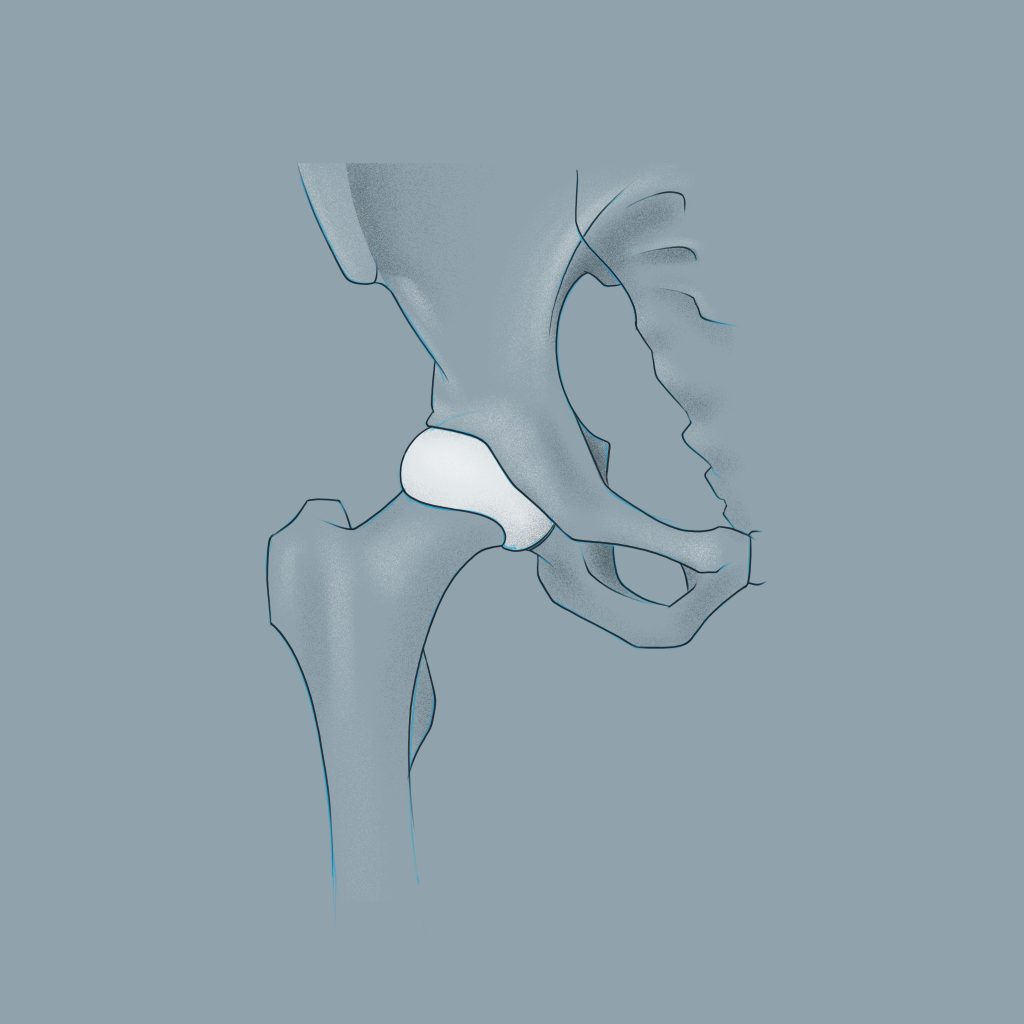

Gesunde Hüfte

Bei der Coxarthrose, auch unter dem Begriff Hüftarthrose bekannt, handelt es sich um einen fortschreitenden Knorpelverschleiß im Hüftgelenk. Die Knorpelschicht bedeckt eigentlich die Gelenksflächen des Hüftkopfes und der Hüftpfanne, wodurch das reibungslose Gleiten der Gelenkflächen ermöglich wird. Bei der Hüftarthrose nutzt sich der Knorpel aber mit der Zeit zunehmend ab, wird dünner und kann an einigen Stellen sogar reißen. Dadurch kommt es zur Druckerhöhung auf den darunterliegenden Knochen und die Beweglichkeit des Gelenkes lässt nach.